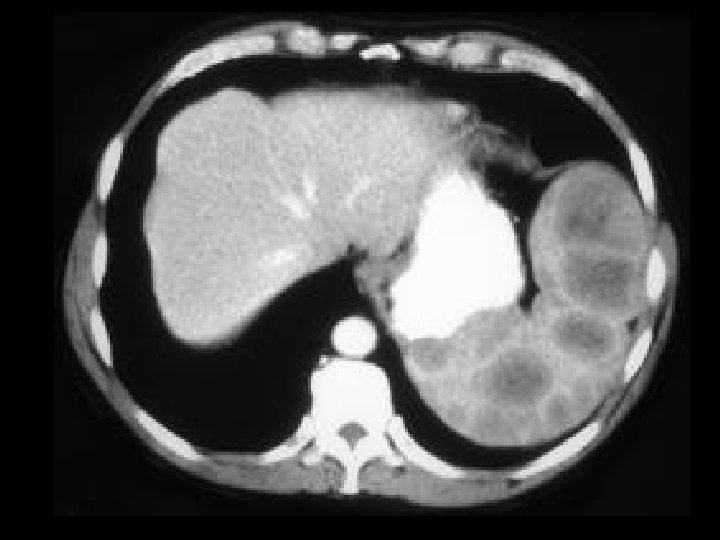

Von-Hippel Lindau • Findings: – Numerous bilateral renal cyst – Solid enhancing right renal mass = RCC • ddx: – NONE! – This is an Aunt Minnie!